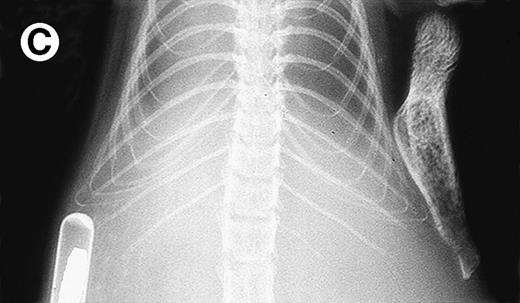

Growth of purified myeloma plasma cells (PC) from patient no. 1 in a SCID-hu host. SCID-hu host was inoculated with sorted PC. (A) Human Ig concentrations. (B) Dot plot of CD38/CD45 flow cytometry profile of the cells. The sort window used to purify plasma cells is shown. (C and D) X-radiograms showing severe resorption of the myelomatous implanted bone (C) compared with the nonmyelomatous bone of the control host (D), implanted at the same time as (C).